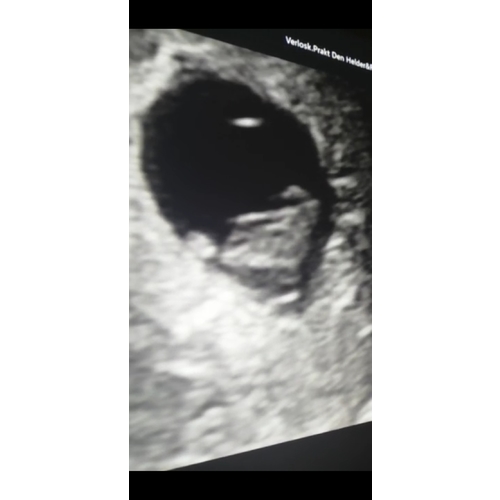

8 weken 2 dagen inwendige echo

Bij mij op de kop. 😂 Dit was ook bij 8 weken.